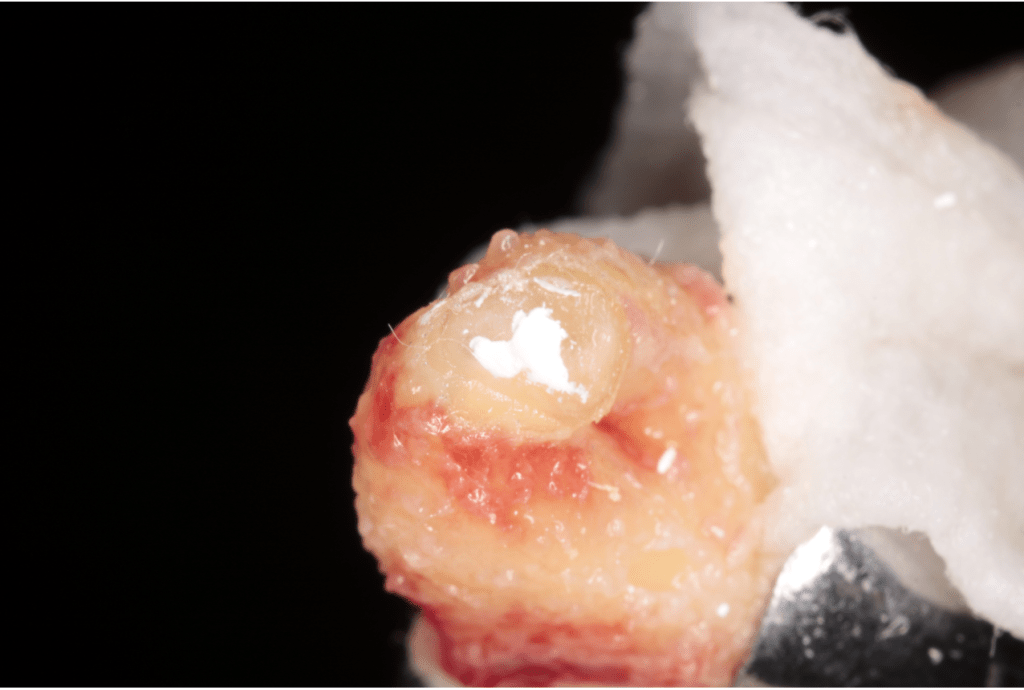

Vertical root fracture